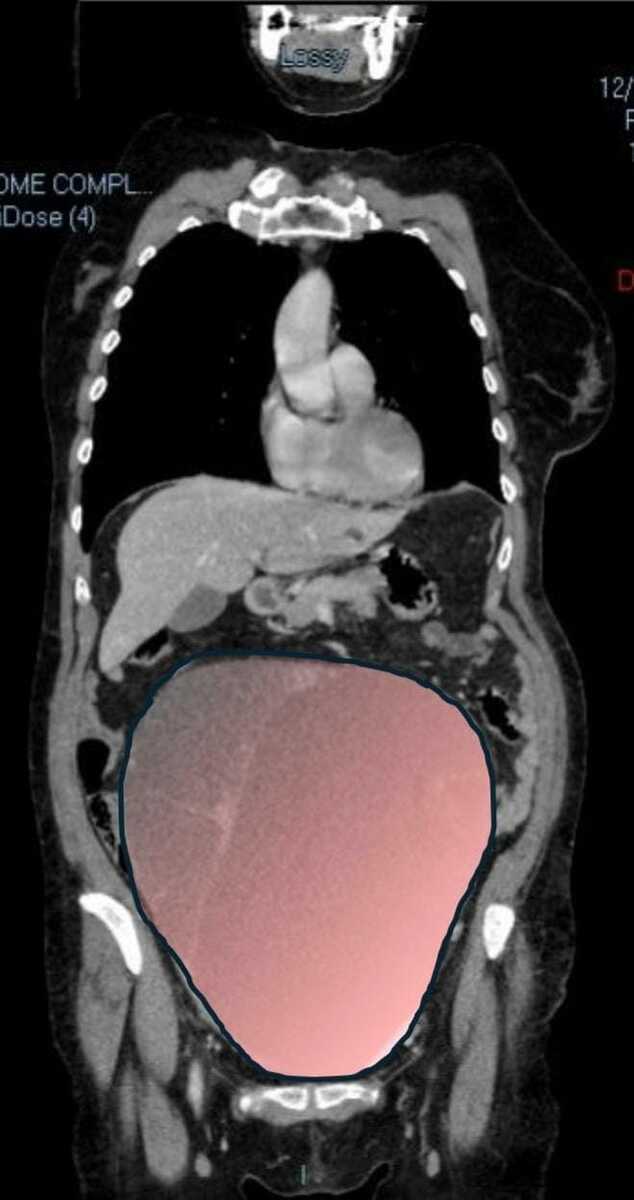

Per mesi la gigantesca cisti ovarica, con un diametro di circa 28 centimetri, è rimasta nascosta, senza dare segnali evidenti. La paziente non si era accorta di nulla. L’allarme è scattato quando la massa, associata alla presenza di una seconda neoplasia intestinale, ha iniziato a comprimere il colon, provocando sintomi acuti ed improvvisi fino ad una grave difficoltà intestinale non più ignorabile.

Fondamentale in questa fase il contributo della Radiologia dell'ospedale Sant’Anna, che fornisce l’imaging preoperatorio indispensabile per affrontare un quadro clinico di eccezionale complessità.

Durante l’intervento emerge tutta la gravità della situazione. La gigantesca neoplasia ovarica viene asportata: pesa circa 6 chilogrammi, con un volume paragonabile a quello di una gravidanza gemellare a termine. Ma non è l’unica minaccia. I sintomi più pericolosi sono legati alla sofferenza intestinale, che richiede un intervento immediato e coordinato di più specialisti.